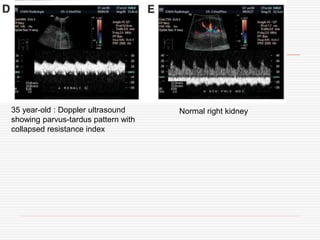

35 year-old : Doppler ultrasound

collapsed resistance index

Normal right kidney

35 year-old :Doppler ultrasound showing parvus-tardus pattern with collapsed resistance index Normal right kidney